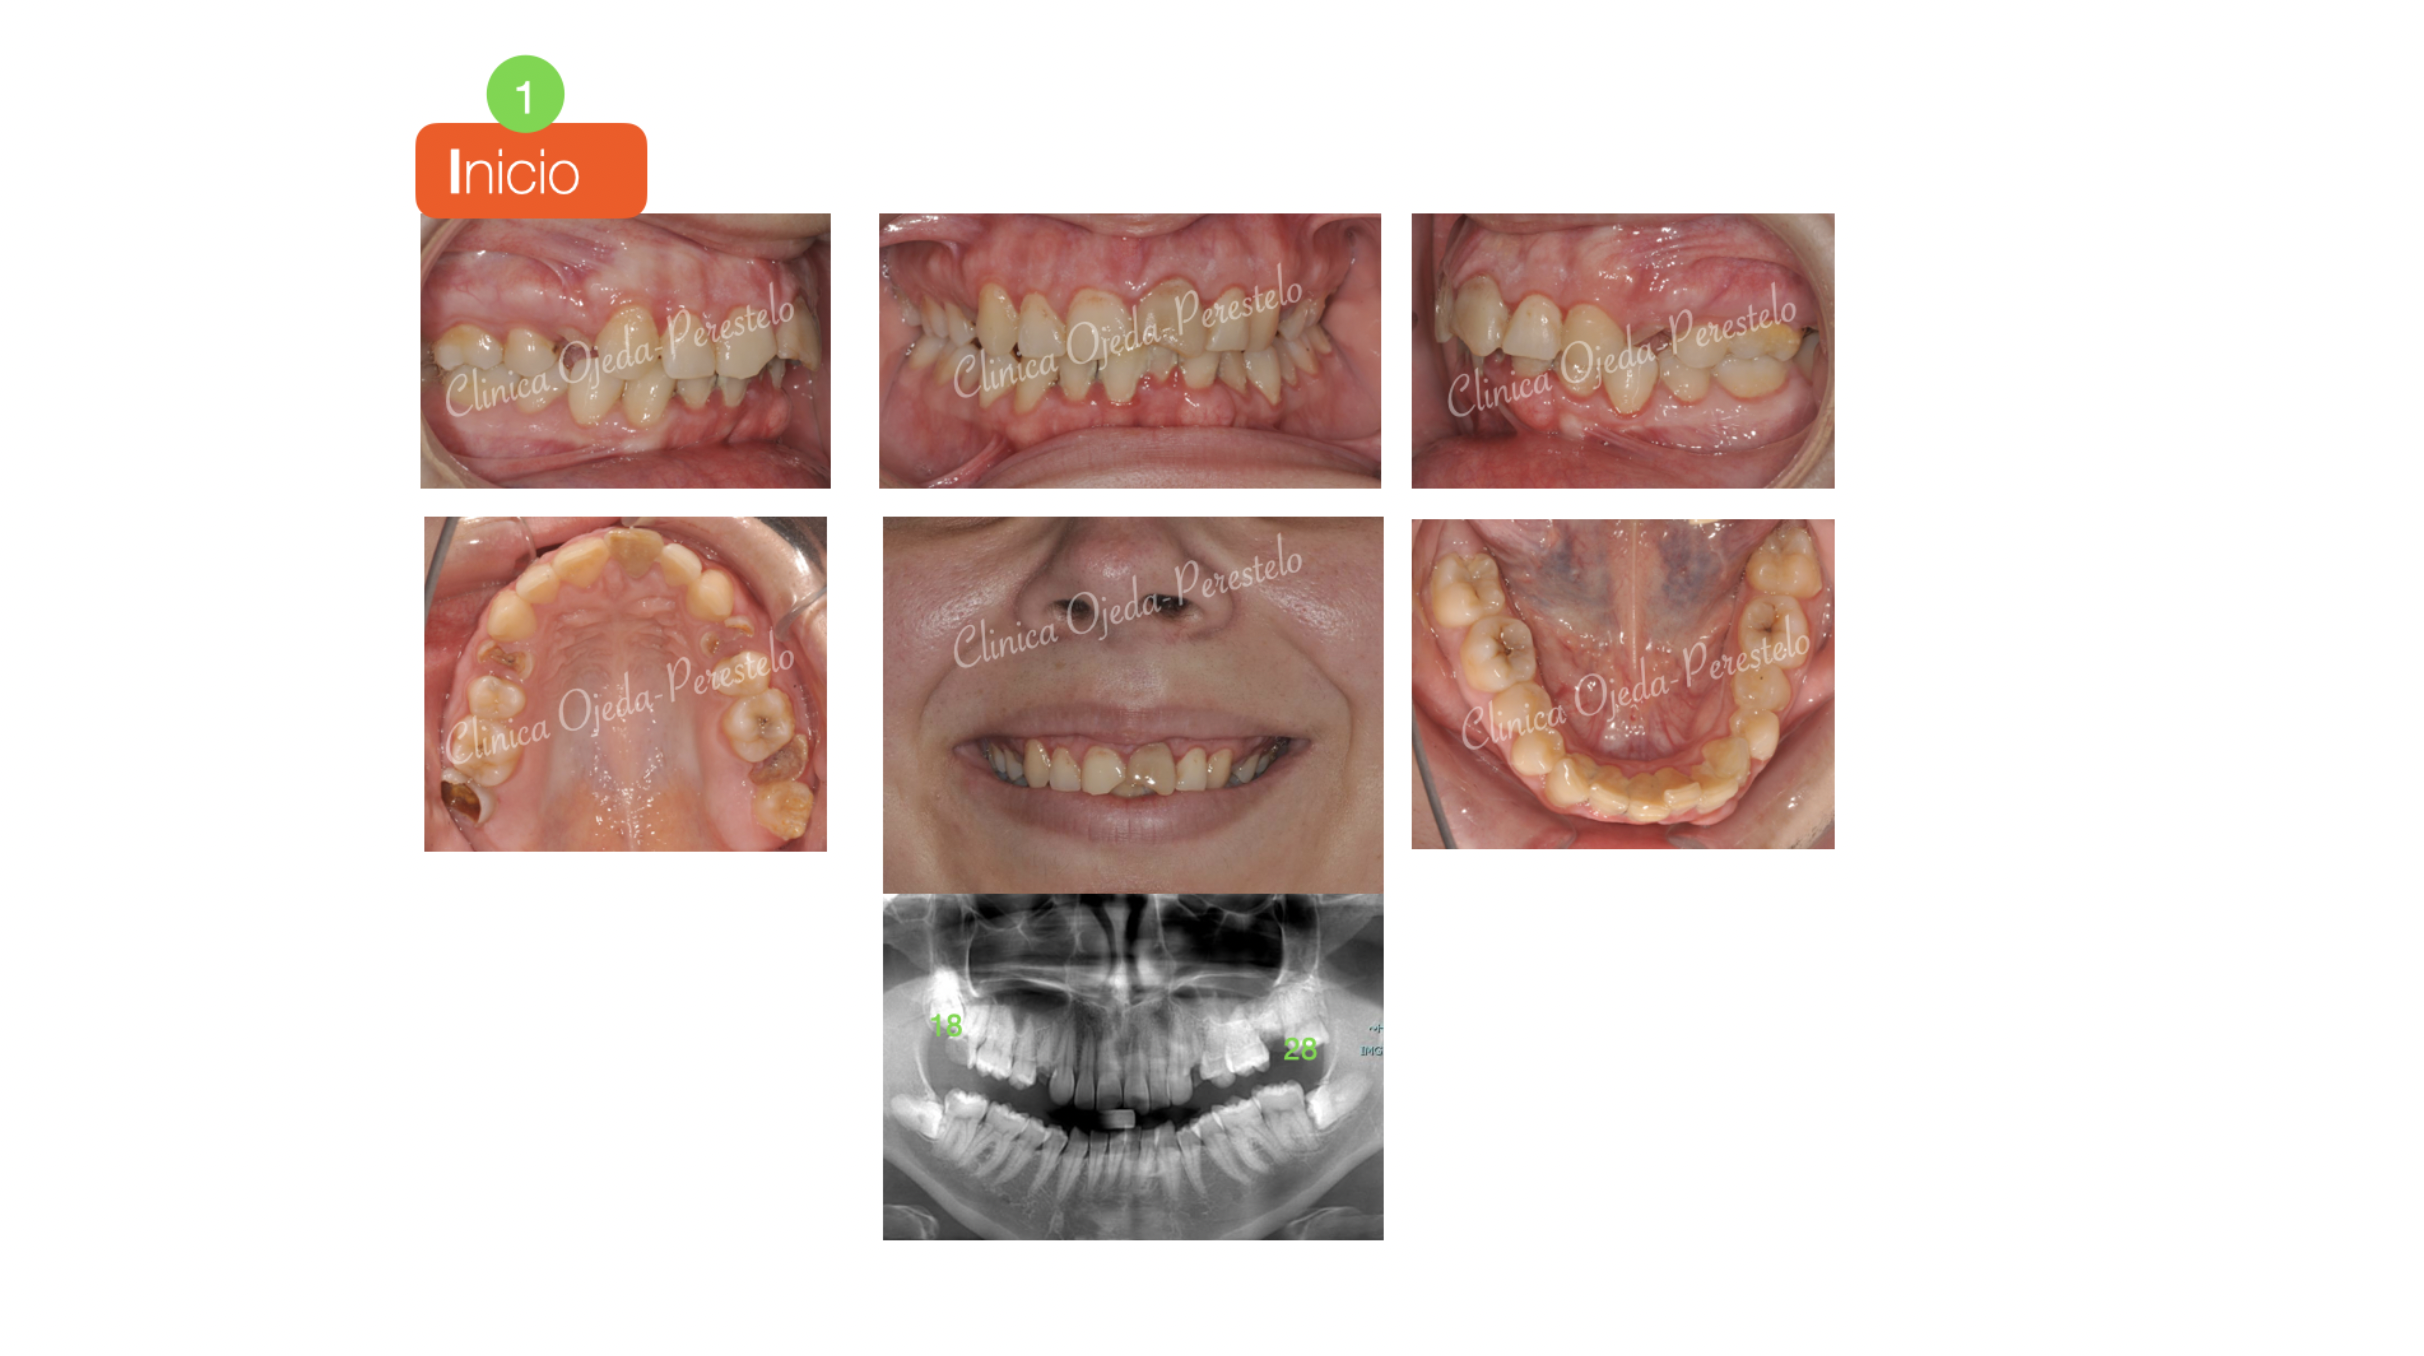

Caso Multidisciplinar: Ortodoncia-Implantes-Bioestética 11-21

La rehabilitación oral completa en los pacientes adultos requiere en algunas ocasiones de planes de tratamiento bien coordinados entre las diferentes disciplinas odontológicas. Presentamos un caso que tras la fase de higienización bucal y la restauración de los incisivos centrales superiores (Bioestética 11-21), comenzó su tratamiento de ortodoncia con alineadores transparentes (Sistema Invisalign). El objetivo de la etapa ortodóncica no era otro que alinear y nivelar sus arcadas dentarias y adecuar el espacio necesario para la colocación de sus implantes en posición 14-24. Además se decidió mover sus cordales superiores (18,28) a la posición de los segundos molares y así evitar tener que colocarse implantes.

Queremos destacar la mejoría de la sonrisa y el correcto engranaje dentario con 3 series de  alineadores superiores e inferiores. En total sumaron 83 alineadores transparentes maxilares y 69 mandibulares que la paciente se cambiaba semanalmente. Una vez finalizada la fase ortodóncica la paciente procedió a colocarse sus implantes y coronas.